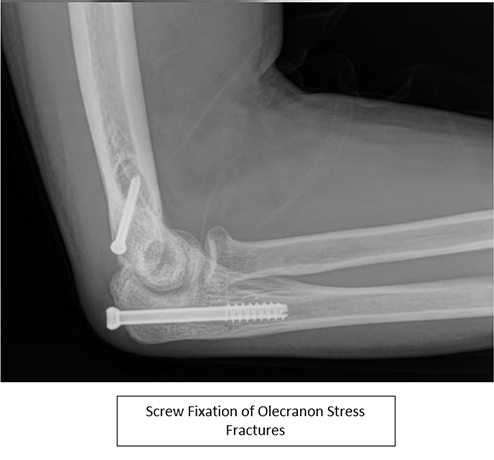

- Surgical treatment typically consists of partially threaded compression screws placed perpendicular to the facture line along the longitudinal axis of the ulna